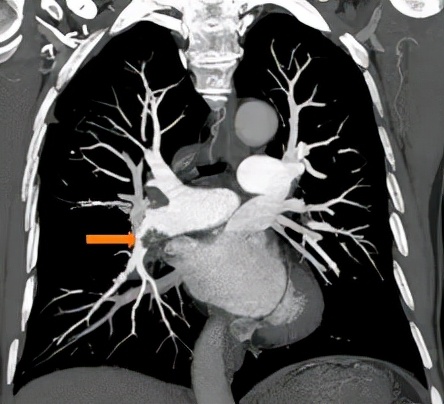

△肺动脉增强CT示:右下肺动脉主干及前基底段分支不完全性栓塞